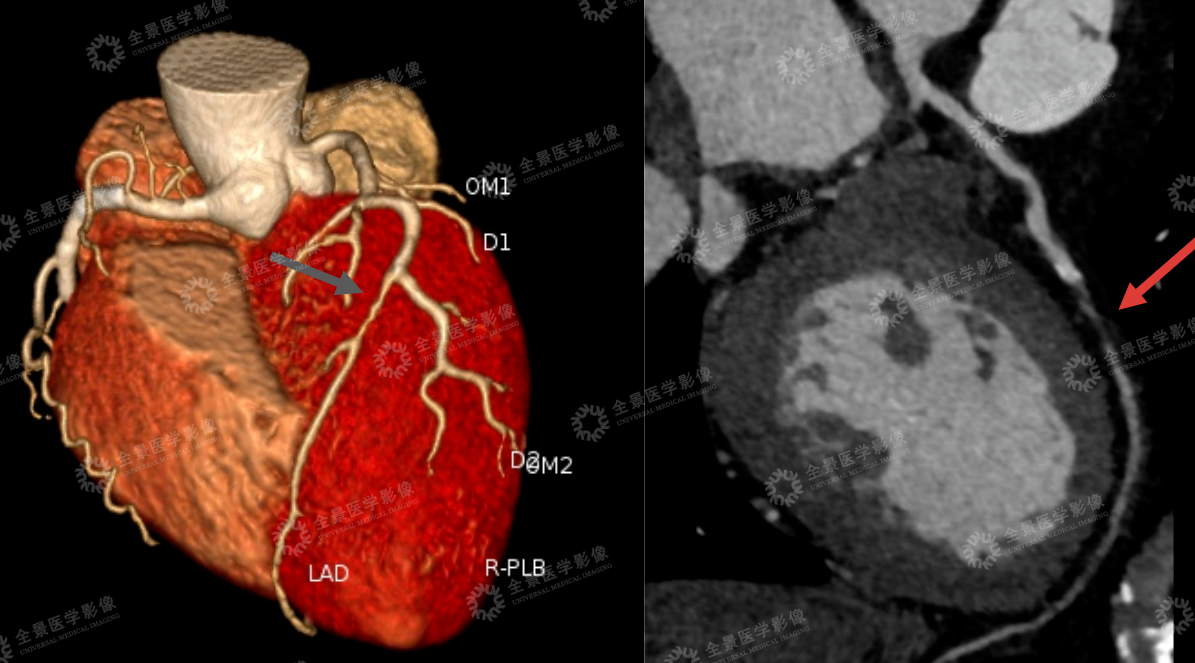

冠脉 CTA 、头颅血管成像(MRA)影像提示:心脏有易破裂「不稳定斑块」,并且管腔已 90%-100% 闭塞,对角支也有钙化斑块,同时脑血管也有问题:右侧大脑中动脉变细,远端几乎看不清....

心脏血管危机:左前降支(LAD,被称为 「心脏生命线」)近中段及对角支 D2 起始段,同时存在钙化与非钙化斑块 —— 其中 LAD 中段的 「非钙化斑块」 属于不稳定斑块(易破裂形成血栓),且管腔 90-100% 闭塞(相当于血管几乎堵死,随时可能突发心梗)。

脑血管连带风险:脑动脉硬化明显,右侧大脑中动脉 M1 段管腔纤细、M2 段及远段显示不清(提示中重度狭窄),左侧大脑中动脉 M2 段局部狭窄。